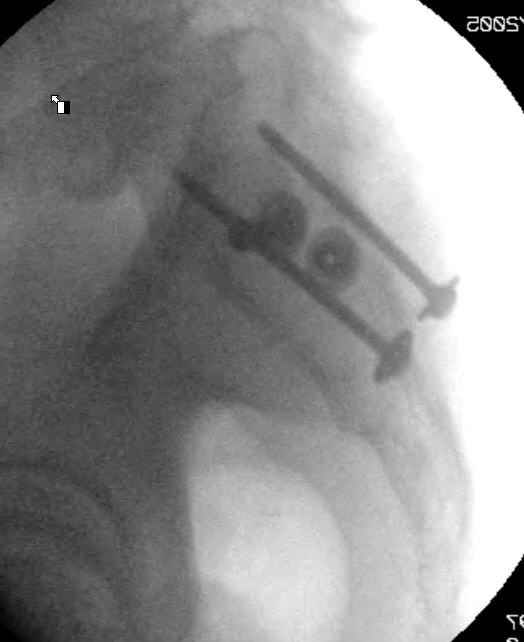

Hello gentlemen- Case is 52 YO male, fell out of treestand while deerhunting. He is 6 ft, approx. 260-275 lbs. Was hemodynamic unstable at local ER, sent to our Trauma center where circumferential pelvic binder placed and pt. stabilized with fluid, blood, and rewarming. Angiography not performed. An extraperitoneal bladder disruption was found, uro elected to treat non-operatively. Initial xray (not shown) demonstrated 5-7 cm wide at symphysis and SI joint. The first image attached is of CT once binder is in place. On post trauma day 5 the pt was taken to OR for ORIF of his iliac wing fracture and SI dislocation. The swelling/3rd spacing of fluid in the area of symphysis was profound, but quite acceptable posteriorly. Patient was prone for procedure, as I thought too difficult to fix the wing in lateral position. Of course the repair of wing was easy, but reduction of SI very demanding. The Floro images document the residual lack of reduction. That was the closest I could get it using 6mm joystick in wing, and clamp on sacrum and clamp through notch. The fixation was (initially) rigid. Anterior ex fix with supra-acetabular pins was placed due to condition of soft tissues, massive "beer-belly" overhanging the crest. Post trauma day ten patient's xray shows failure of posterior construct. Plan was to perform revision orif once soft tissues resolve considerably for full anrterior fixation and posterior fixation. However, while Im away for holiday (on Post trauma day 15), pt is developing septic clinical appearance, and trauma suspects pelvic abcess near symphysis and performs I and D - finds nothing but no primary closure performed. Posterior tissues/incision continue to look healthy. Now is post trauma day 17, pt is still tubed/on dopamine/and wbc still elevated, anterior incision still packed open. Clearly must get to bottom of possible sepsis, but then what? Thanks for you time - sorry for such lengthy clinical description. Thomas Schaller Kalamazoo, Michigan

5. Your caudal iliosacral screw is/was in his spinal canal... it's low and posterior and the lateral fluoro image confirms this... a postop CT will show it (or it's trail at this point)... canal screws do not hold.

On 11/29 took patient back to OR and explored both his anterior and posterior wounds, removed loose illiosacral screws. Left behind the screws fixing illiac crescent. Found anterior wound clean and closed it. Found posterior wound with moderate seroma and some adjacent fat necrosis. Thus far, cultures negative, but not kidding myself on that fact. Wound VAC placed and going back tomorrow to reexamine wound and may close it or re-VAC one more time. Fixator remains in place.

My plan to revise fixation is in line with your suggestion - plate symphysis and anterior approach to SI joint. It appears from post - failure CT scan that the path of the more cephalad IS screw may be helpful to place a longer screw to engage opposite illiac wing as an option, or just anterior SI plates. not likely to do this tomorrow as he remains in a fragile clinical situation regarding his pulmonary status, and profound edema/induration around his pelvis/abdomen and thighs.